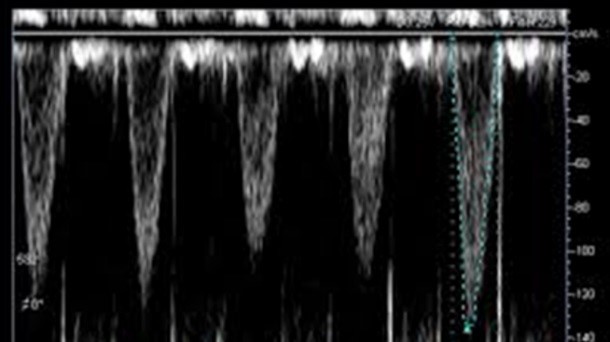

Como monitor hemodinámico avanzado no invasivo.

Para estimar los parámetros hemodinámicos de forma no invasiva que obtenemos por métodos más invasivos no exentos de posibles complicaciones inherentes a su colocación, a pie de cama del paciente tales como: PCP, gasto cardíaco, variabilidad del volumen sistólico, PVC, resistencias vasculares sistémicas y pulmonares, agua extravascular pulmonar y guiar las terapéuticas administradas.